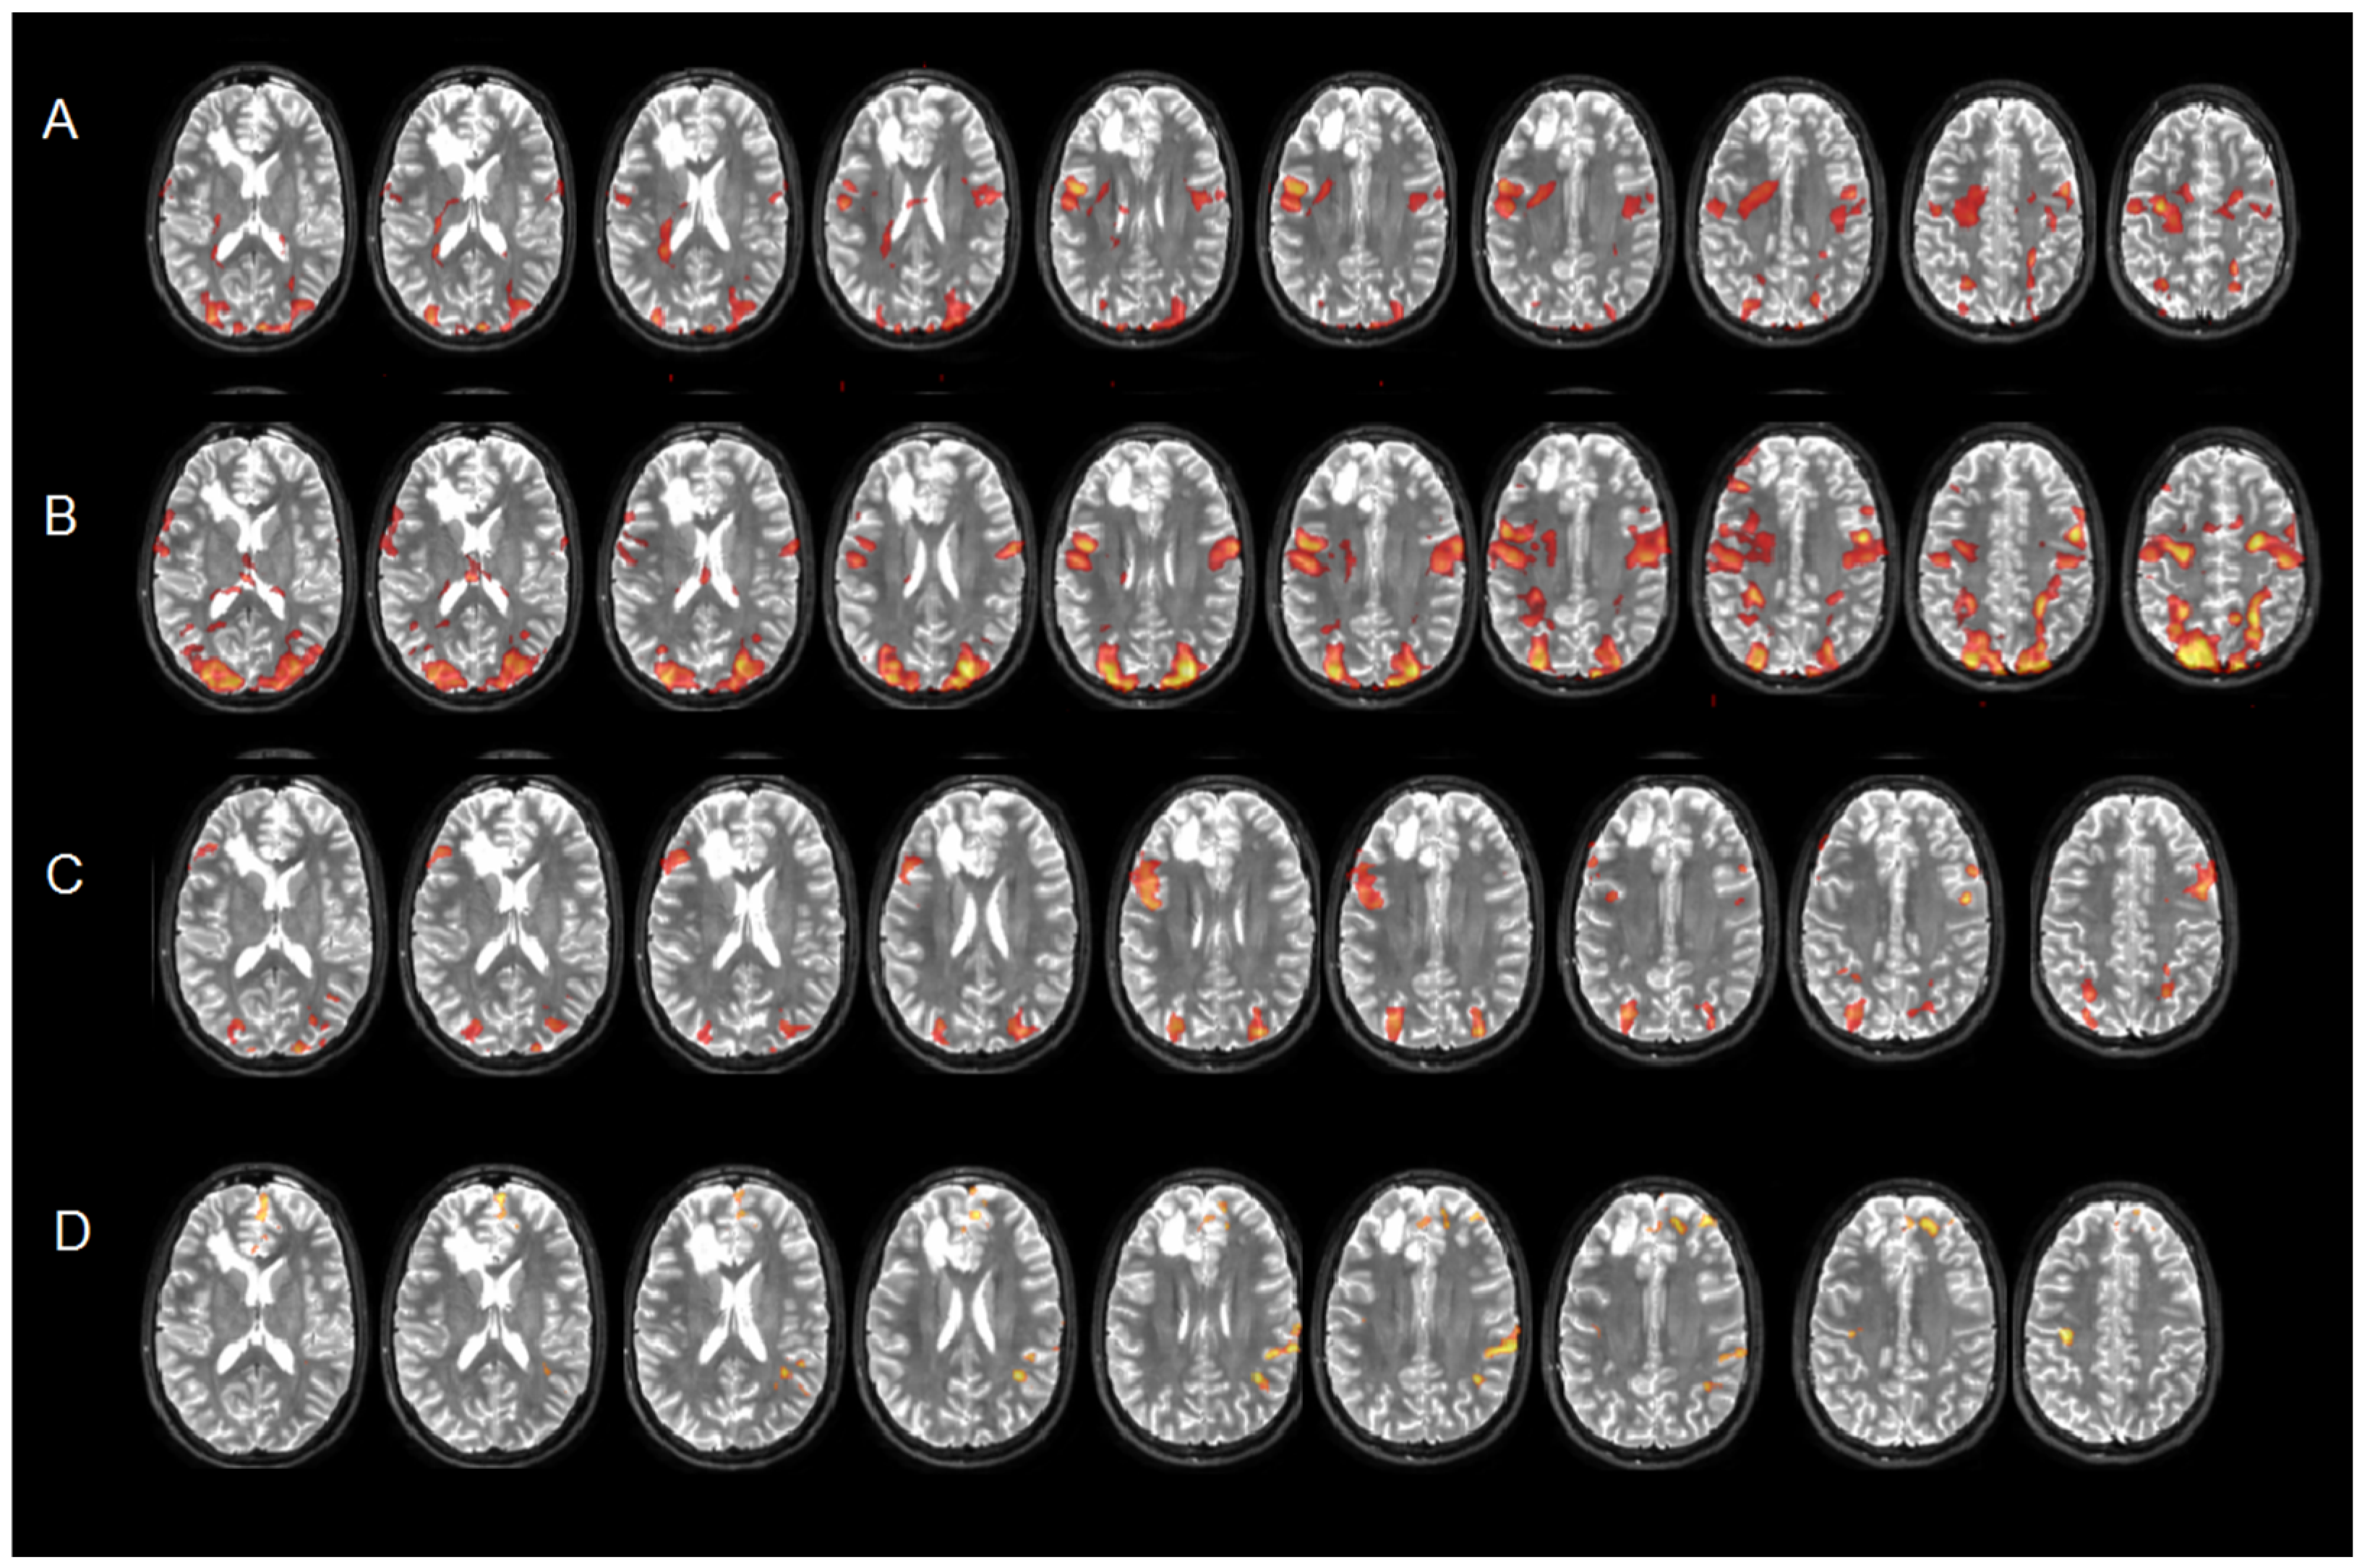

3.2.2. Case Series Examples

Extra-Language Functions